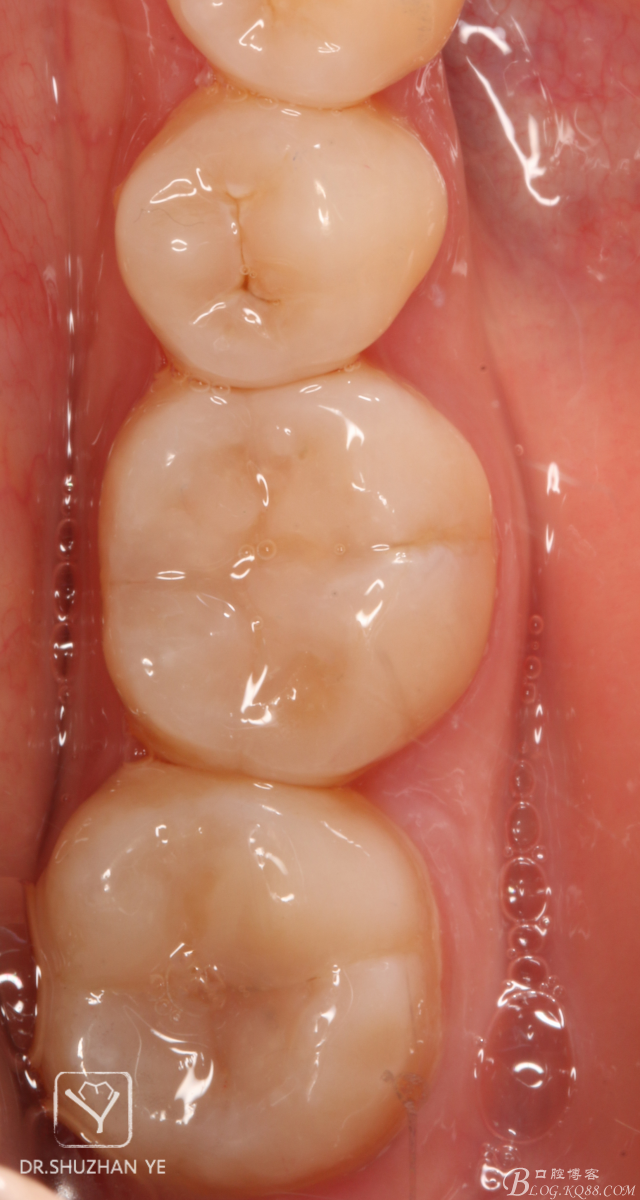

1、術(shù)前照片,46,47頜面齲壞,且頜面完整,無缺損